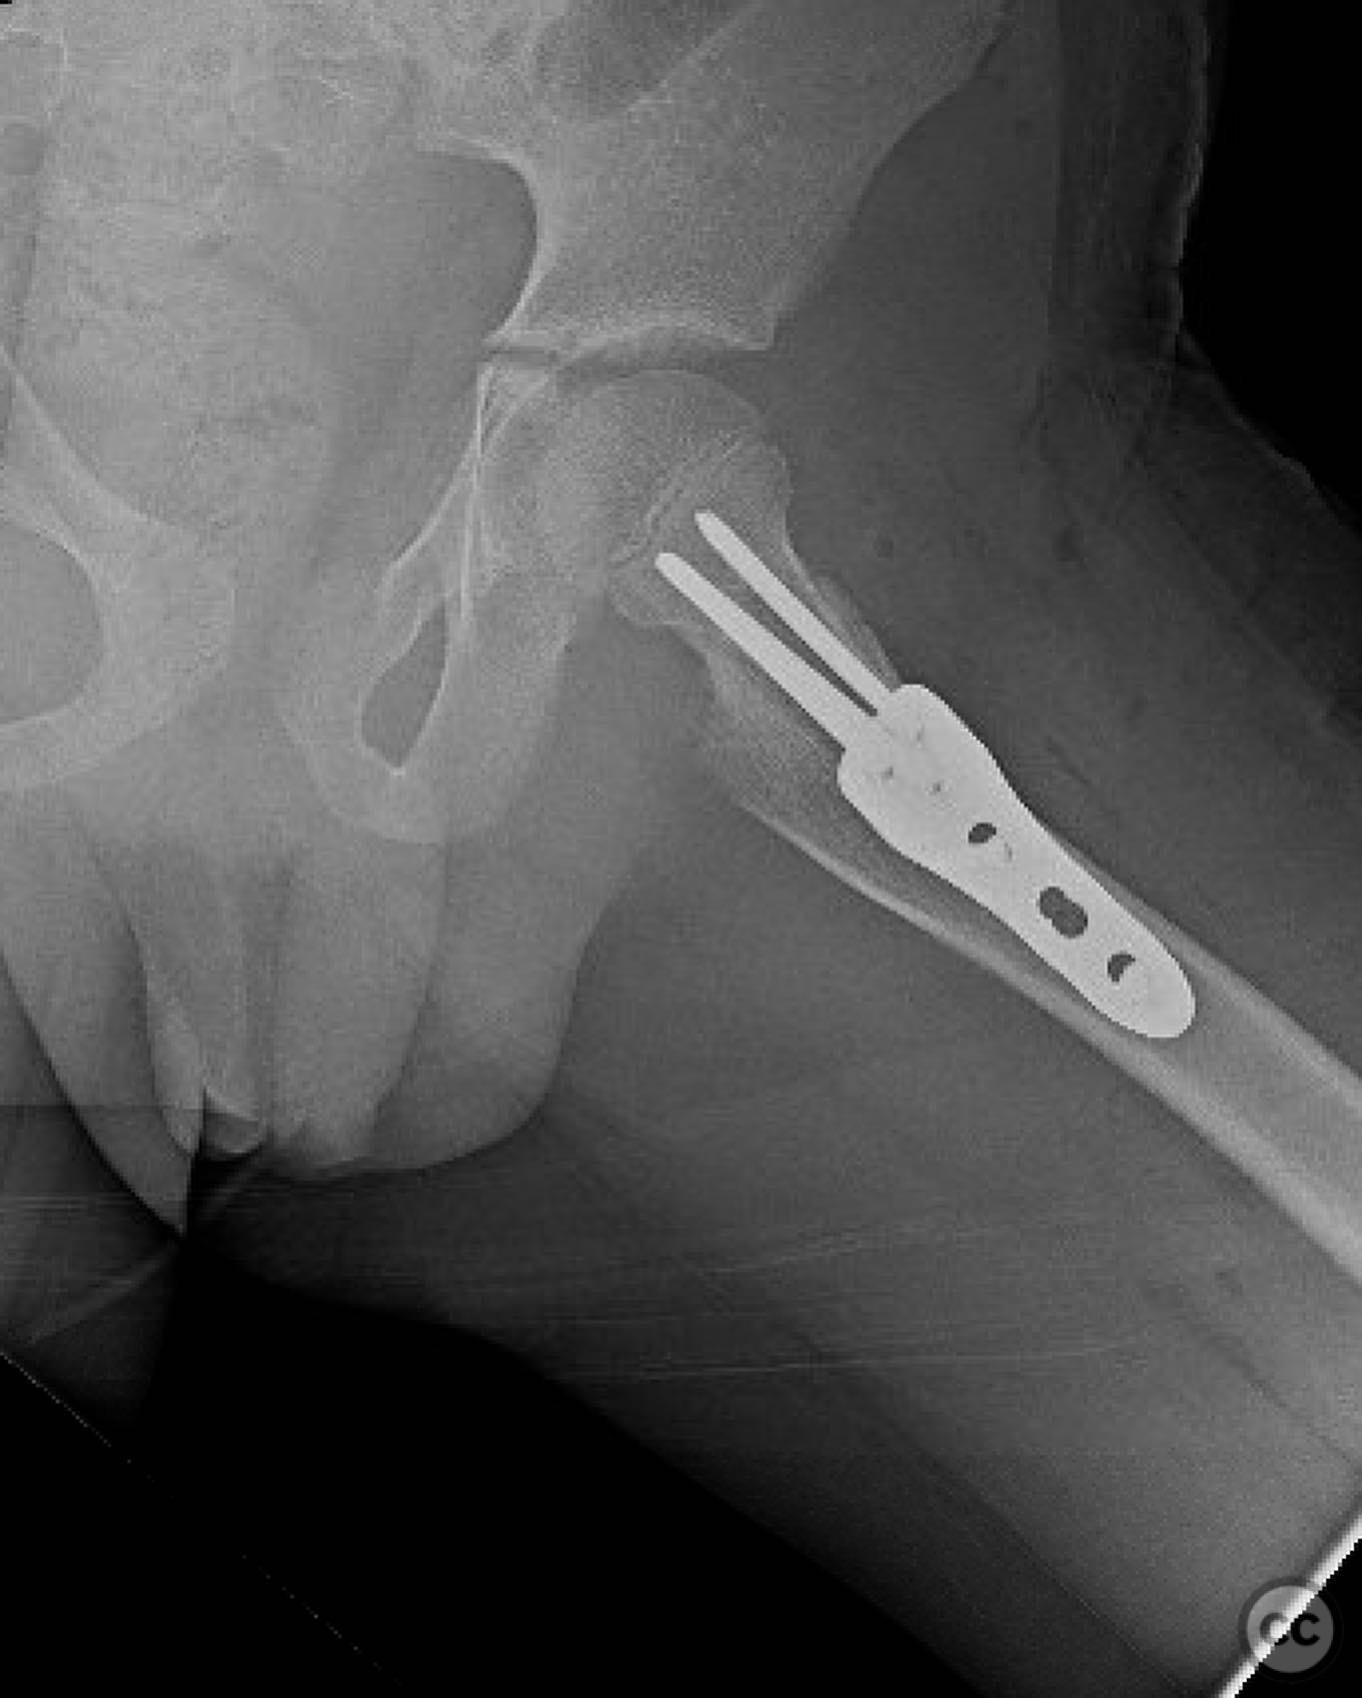

Clinical and radiological findings:  An 8-year-old boy fell approximately 15 feet from a treehouse, sustaining a displaced femoral neck fracture. There were no associated injuries to the head, spine, chest, or abdomen. The initial radiological assessment confirmed a displaced fracture of the femoral neck. Neurovascular examination was unremarkable.

Planning remarks:  The preoperative plan involved achieving a direct anatomic reduction and stable fixation of the femoral neck fracture. The surgical approach considered was a modified Smith-Petersen approach for optimal visualization and reduction, followed by a separate lateral approach for implant application.

Anatomical surgical approach:  A modified Smith-Petersen approach was utilized, involving an incision along the anterior aspect of the hip, allowing for direct visualization of the femoral neck. Subperiosteal dissection was performed to expose the fracture site without compromising the surrounding musculature. A separate lateral approach was employed for the application of fixation devices.

Orthopaedic implants used:   Angle stable static device (specific brand not mentioned).